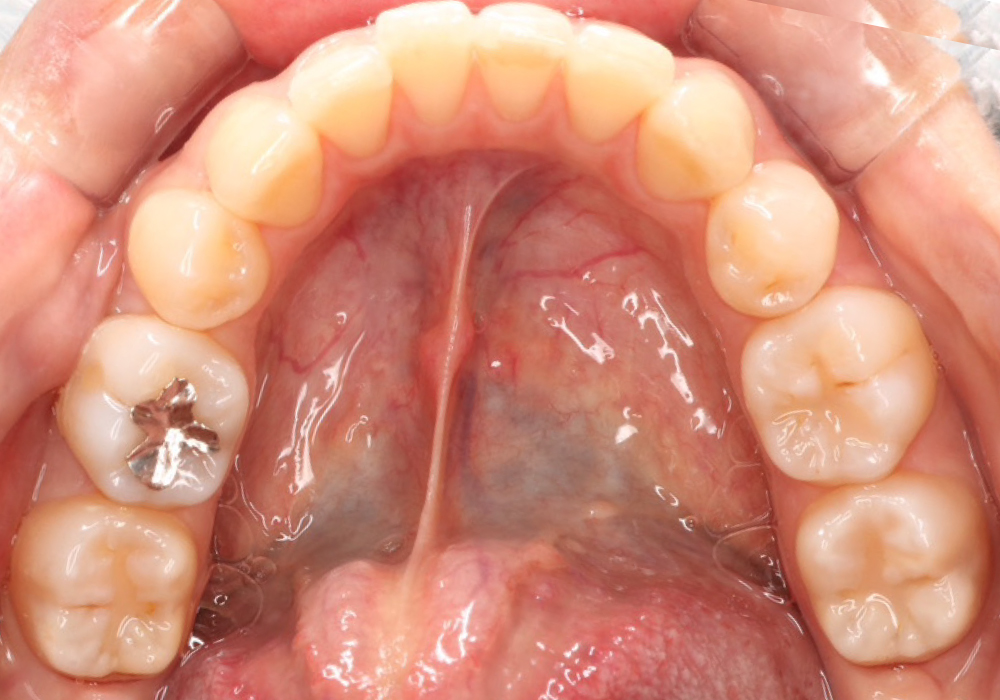

治療前